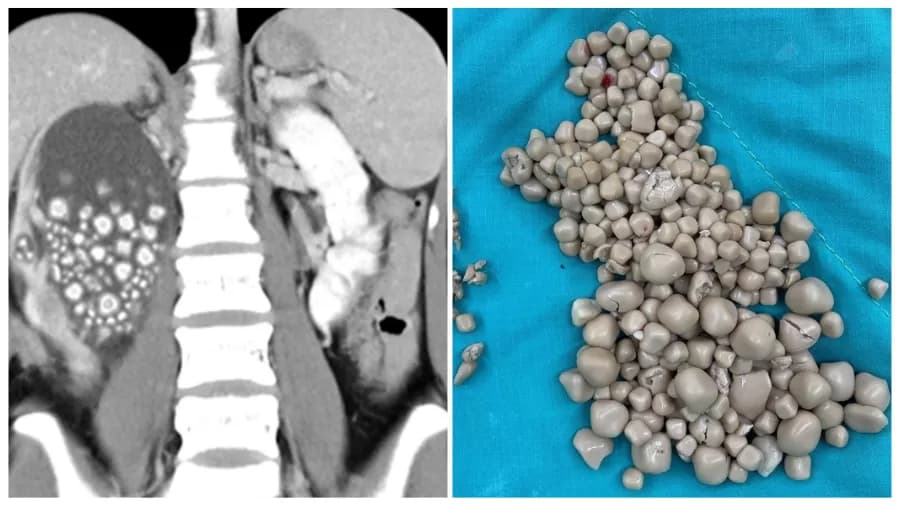

Imagem: Reprodução/Hospital Chi Mei

Após se submeter a alguns exames, os médicos perceberam que o rim direito da moça estava gravemente inchado e fizeram uma radiografia para determinar a causa. Eles ficaram surpresos ao descobrir que o órgão continha mais de 300 pedras, variando entre 0,5 e 2 centímetros.

Após fazer um procedimento de duas horas chamado de nefrolitotomia percutânea, os médicos removeram a enorme quantidade de pedras de seu rim.

Segundo o cirurgião Lin Caiyang, as pedras “pareciam pequeninos pães cozido no vapor”. Lin ainda listou que genética, baixa ingestão de água e a dieta diária são fatores mais importantes para a formação de cálculos renais.